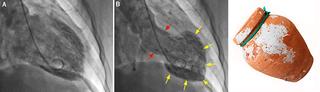

Harmslegill heitir á frummálinu Takotsubo sem er heiti á krabbagildru sem sjá má hér til hliðar við röntgenmyndirnar. Heitið helgast af löguninni sem er sú sama og téðrar gildru

Harmslegill eða Takotsubo er tímabundin afturkræf truflun á samdrætti hjartans sem lýsir sér þannig að hjartað líkist blöðru. Heilkenninu var fyrst lýst árið 1990 í Japan hjá 64 ára gamalli konu sem fékk brjóstverk og var hjartalínuritið með breytingum sem líktust bráðri kransæðastíflu.

Kransæðarnar voru hinsvegar eðlilegar en vinstri slegill dróst óeðlilega saman og gekk samdráttarskerðingin tilbaka á tveimur vikum. Heilkennið var nefnt Takotsubo eftir japanskri kolkrabbagildru því lögun hjartans líktist gildrunni þegar það sló í þessu ástandi. Heilkennið hefur verið kallað ýmsum nöfnum á ensku m.a. broken heart syndrome, stress cardiomyopathy og apical ballooning syndrome en á íslensku hefur það verið nefnt harmslegill.

Dæmigerður harmslegill lýsir sér oftast sem tímabundin afturkræf samdráttarskerðing í broddi og miðhluta vinstri slegils með kröftugum samdrætti í grunnhlutanum. Þó eru til aðrar birtingarmyndir þar sem samdrátturinn getur truflast á mismunandi stöðum í hjartanu og kallast það þá ódæmigerður harmslegill.

Sjúklingur með dæmigerð mynd af harmslegli með samdráttarskerðingu í broddi og miðhluta vinstri slegils með kröftugum samdrætti í grunnhlutanum